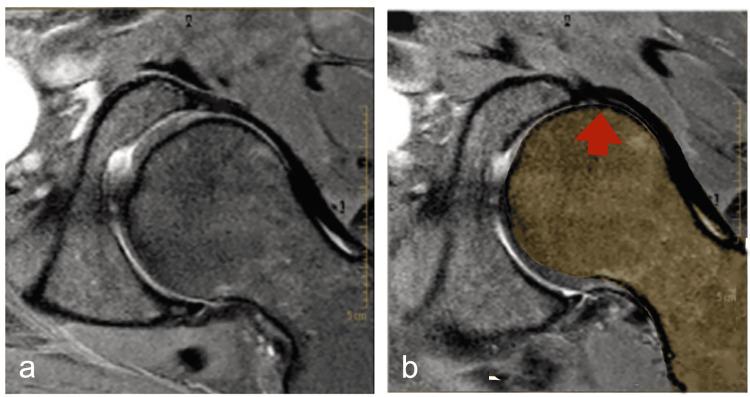

仰卧桥运动(SBE)在康复领域中被广泛认可,可用于改善核心稳定性和髋伸肌力量。虽然其对腰痛的益处已有文献记载,但其在髋关节功能障碍中的作用仍未得到充分探索。本叙述性综述研究了SBE在退行性和功能性髋关节疾病中的应用,包括股骨髋臼撞击症(FAI)、微不稳定和股骨前滑综合征(FAGS)。特别关注臀大肌激活(尤其是下部,即LGM)背后的生物力学原理以及腘绳肌对协同优势的抑制。基于现有证据,特定的SBE变式,包括髋部和脚踝位置、脊柱排列以及神经肌肉控制策略,可能会促进股骨头后移和关节稳定性。此外,该综述强调,在特定的运动员群体中,如足球运动员和舞者(其中凸轮型FAI改变和髋关节内旋受限尤为普遍),将SBE训练纳入预防性训练计划有助于维护髋关节健康并减轻退行性病变过程。我们认为,适当调整后的SBE可成为髋关节功能障碍保守治疗和功能再训练的基本治疗工具。